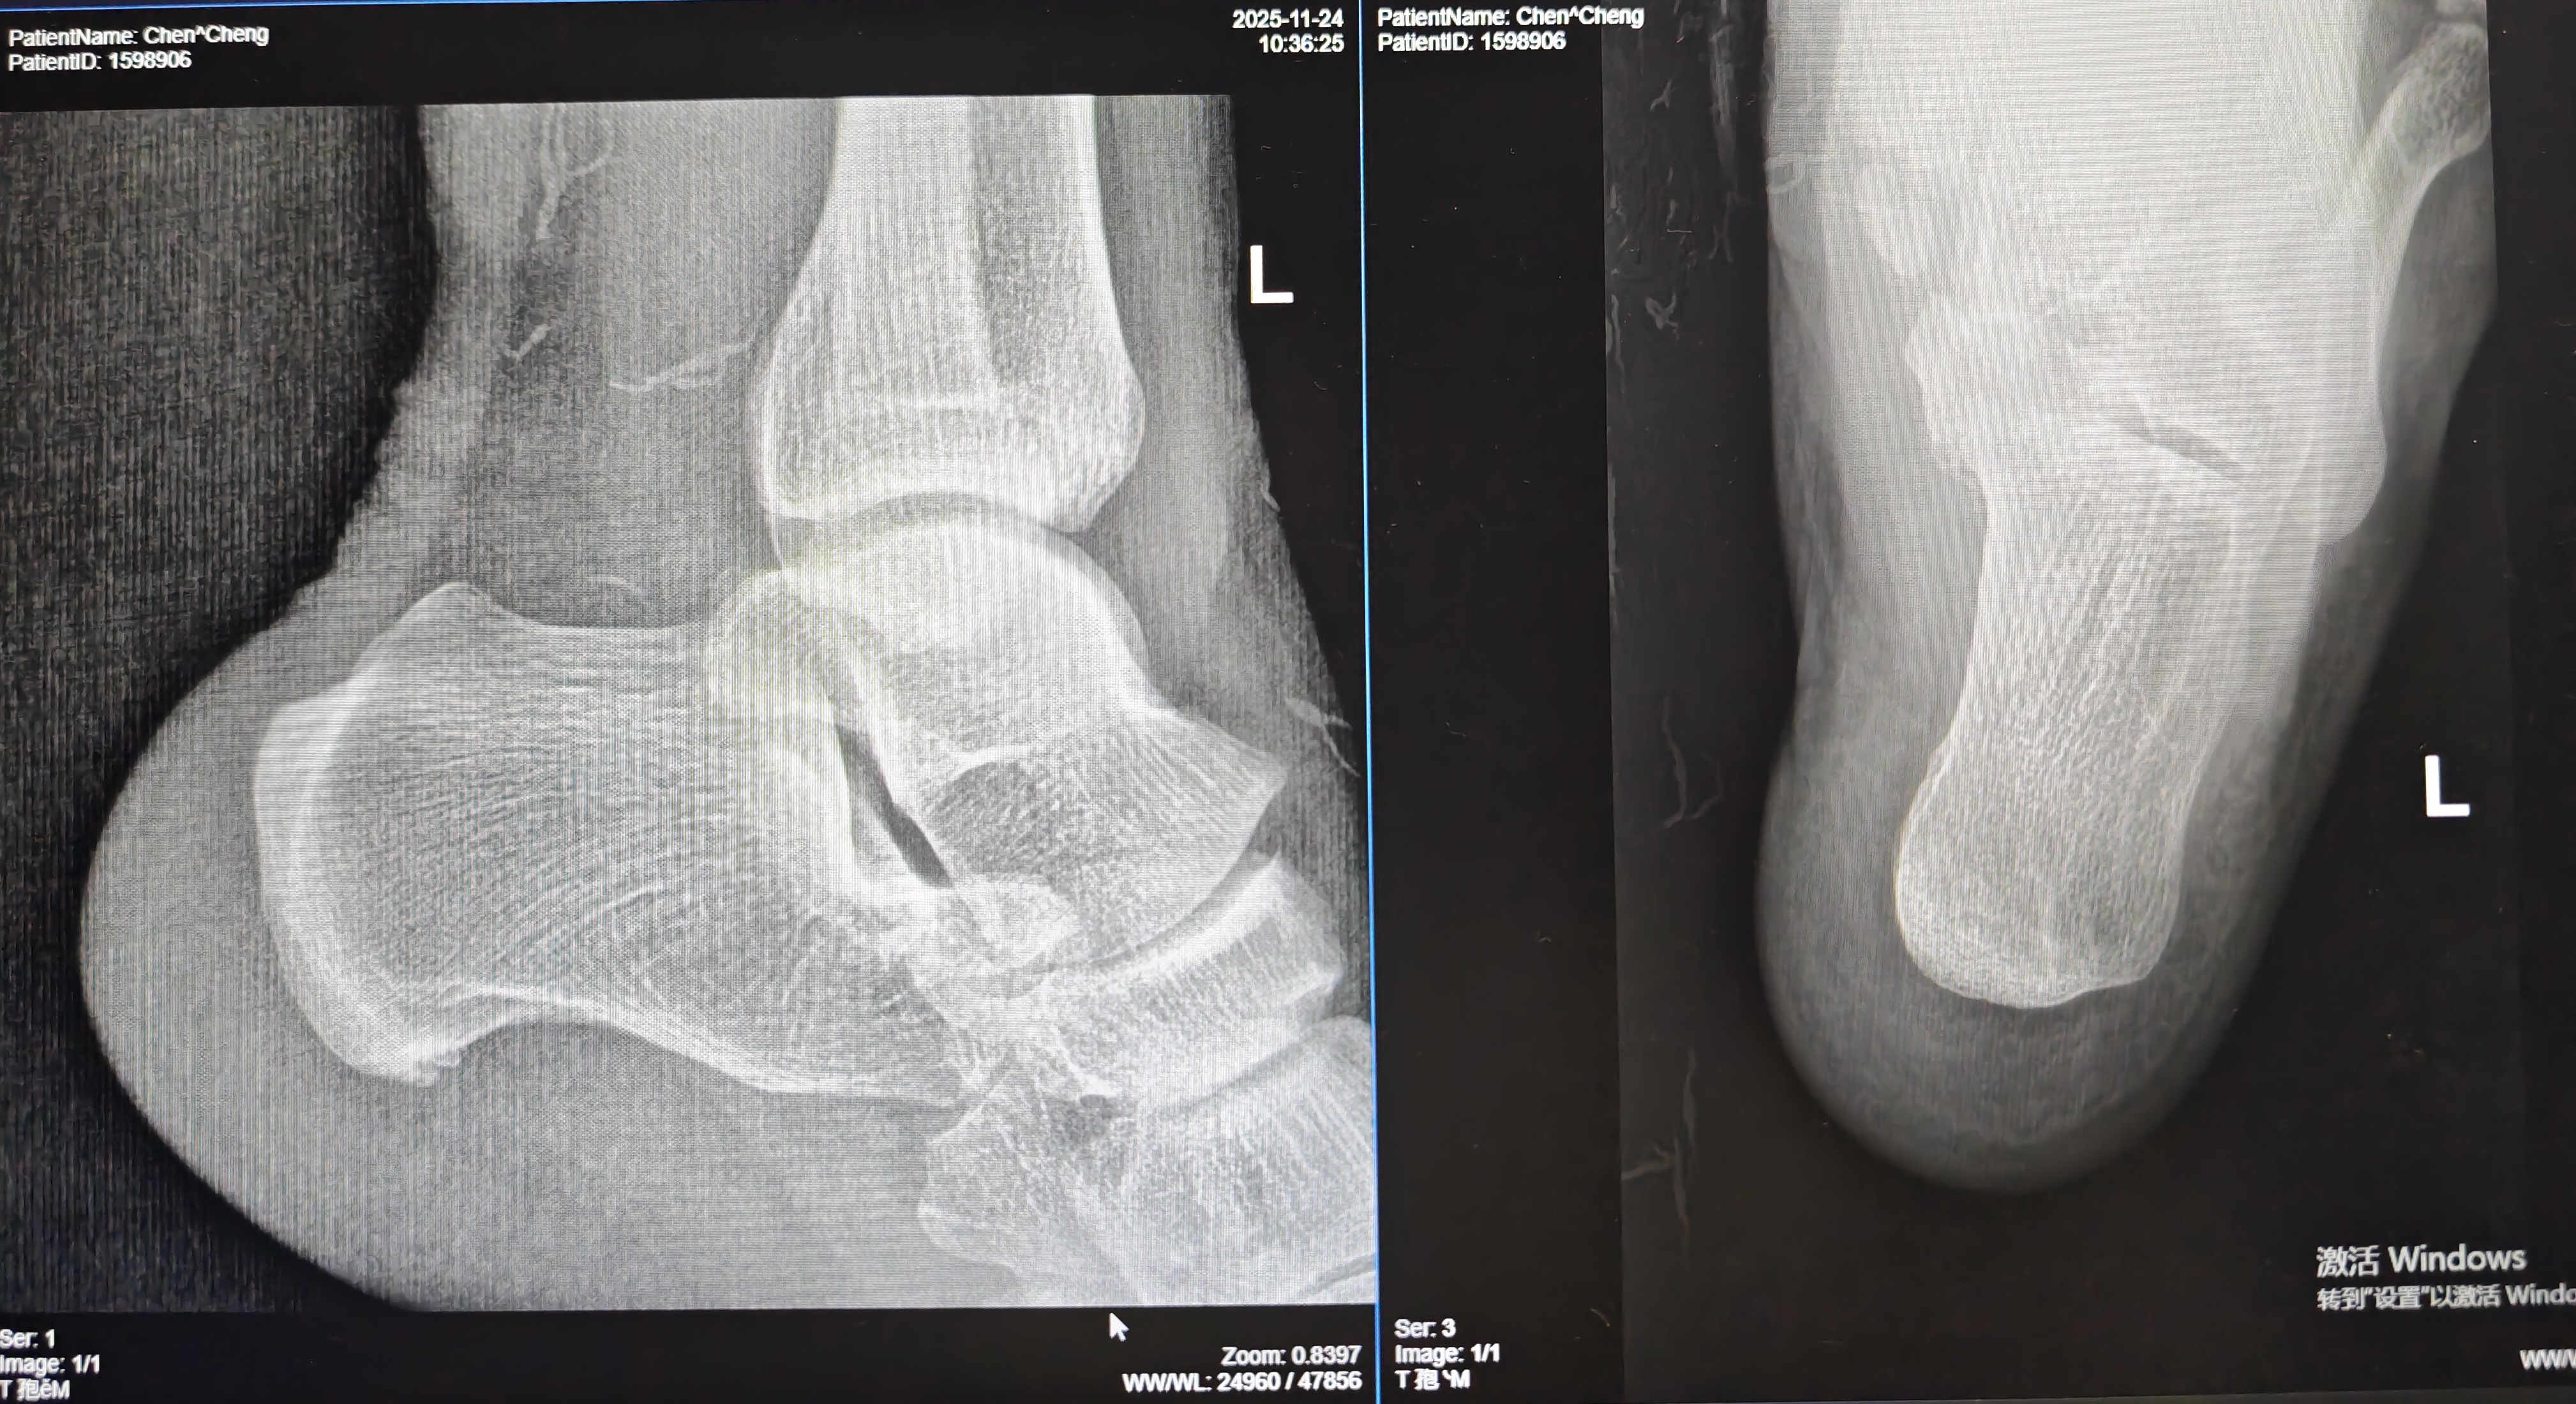

【影像】X线报左侧跟骨前下缘骨质增生。阅片见左侧距舟关节、跟骰关节对合不全,跟骨前下缘骨质增生,方向向前。

【讨论】本案症状表现为久行足跟下方疼痛;查体跟骨结节前缘中点偏内压痛(+)、足底筋膜牵张试验(+);X线片见跟骨前下缘骨质增生(方向向前,提示跖筋膜张力过大、起点钙化);诊断为“跖筋膜炎”。 立位左侧足弓塌陷,诊断为“扁平足”。 交叉腿试验(+)、中立位下蹲试验(+),诊断为“臀肌挛缩”。 行走时左足外旋、屈膝时左侧膝关节朝向前外与臀肌挛缩相关。左侧内踝后下方疼痛,查体胫骨后肌紧张,压痛(+),久压向内踝后下放射,诊断为“胫骨后肌损伤”。